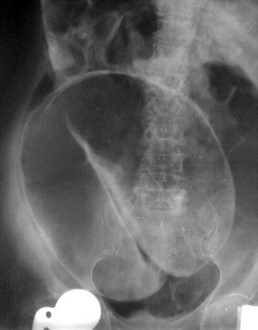

Figure 3: Acute colonic pseudo-obstruction (X-ray).

Haustra and gasin the colon.

When the redundant sigmoid colon becomes symptomatic, the differential diagnosis is ‘acute colonic pseudo-obstruction’ which is associated with ‘intestinal neural dysplasia’ [9]. The erect plain abdominal x-ray appears different from that of a sigmoid volvulus (Figures 2 & 3).